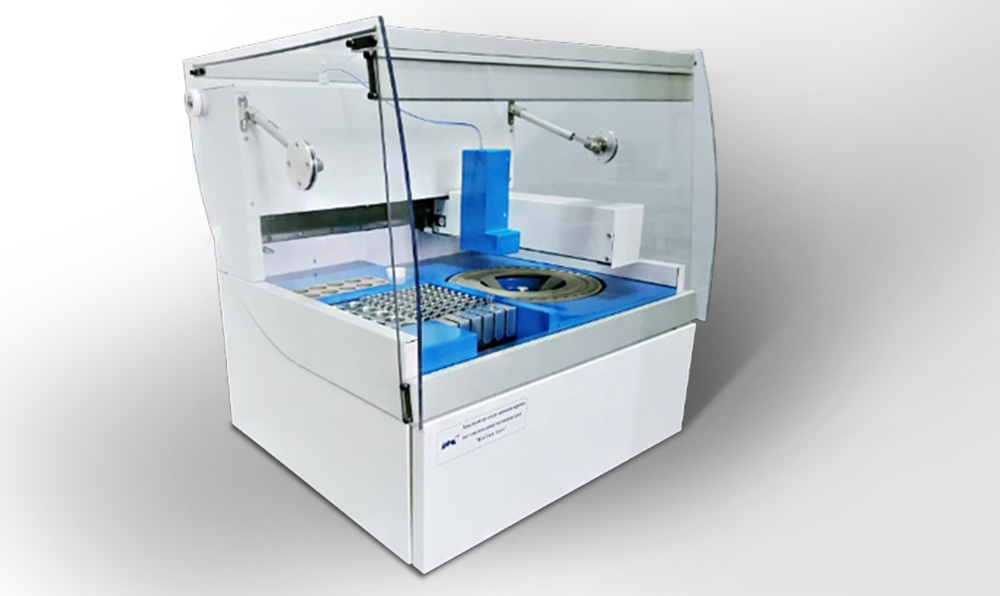

Высокопроизводительные гематологические анализаторы Гемакон ДДС 6180/6580 на 110 и 150 тестов в час производятся компанией «ДИАКОН-ДС», имеющей сертифицированную систему менеджмента качества по международным и национальным стандартам (ISO 13485, ГОСТ ISO 9001). Анализаторы работают на оригинальных отечественных реагентах и контрольных материалах производства «ДИАКОН-ДС», и они всегда есть в наличии. Это обеспечивает стабильные поставки полного комплекса реагентов и расходных материалов в клинико-диагностические лаборатории, гарантируя бесперебойную работу и полную независимость от импортных поставок.